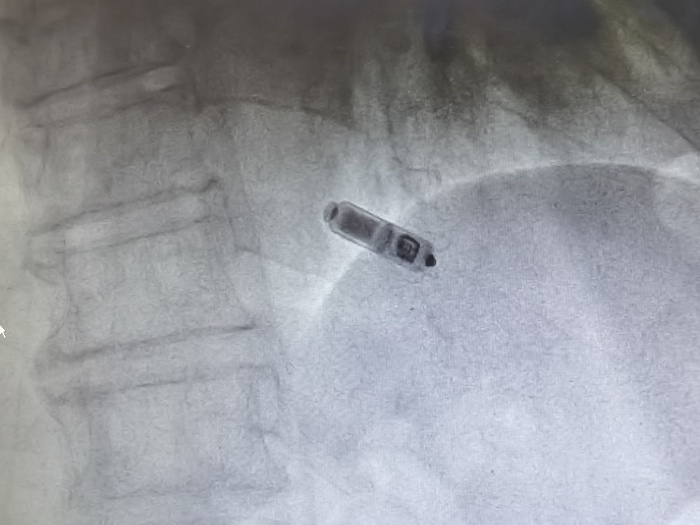

(圖示為植入心臟內(nèi)的Micra? AV無(wú)導(dǎo)線起搏器)

金奇志主任醫(yī)師告知:“無(wú)導(dǎo)線起搏器是集脈沖發(fā)生器與電極導(dǎo)線于一體的新型起搏器,無(wú)需靜脈植入心內(nèi)膜導(dǎo)線,通過(guò)以“微縮膠囊”的形式植入患者的心腔內(nèi)。無(wú)導(dǎo)線起搏器植入簡(jiǎn)單、美觀,無(wú)囊袋及導(dǎo)線植入相關(guān)并發(fā)癥,不影響肢體活動(dòng),可以明顯提高患者的自信心和治療體驗(yàn),安全性與穩(wěn)定性也比較好?!?